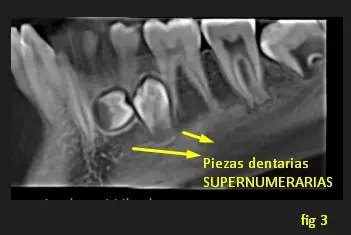

En la segunda imagen, en una vista tangencial se observa a las dos primeras piezas dentarias supernumerarias ubicadas hacia lingual, entre zona de Pd 46 a Pd 43. Y en la imagen 3 se visualiza a las otras dos piezas supernumerarias ubicadas hacia lingual y entre pieza dentaria 33 y Pd 36.